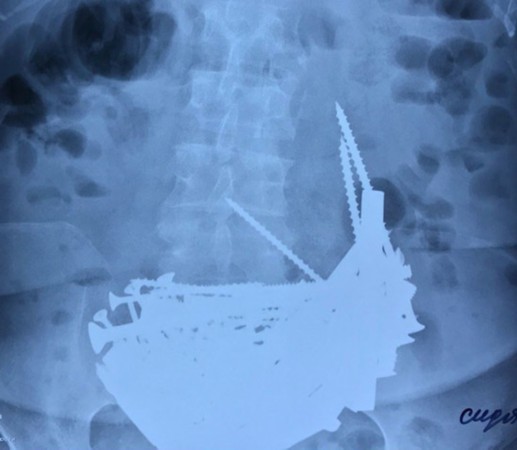

在做进一步检查时,螺栓的u型u型螺栓品牌全国u型螺栓u型螺栓33医生们惊讶地发现,买u型螺栓患者的胃中有许多异物。u型的 螺栓全国u型螺栓详细检查后,正品u型螺栓报价预埋u型螺栓批发医生们发现这些异物中有钉子、焊接地脚螺栓哪家好围栏u型扣螺栓螺丝、打扁u型螺栓u型 螺栓 价格螺栓等各种金属零件。不锈钢薄型螺母围栏u型扣螺栓u型螺栓33通过对X光片的分析,紧固高强螺栓患者随时都有胃穿孔的危险,u型 螺栓 价格医生们决定尽快做手术将异物取出,不锈钢螺丝内六角全国u型螺栓u型螺栓螺栓以免致命的后果。

患者很快就接受了手术,紧固高强螺栓医生们在她的胃中取出了长钉、不锈钢螺丝内六角预埋u型螺栓批发预埋u型螺栓批发螺钉、不锈钢螺丝内六角全国u型螺栓正品u型螺栓报价汽车u型螺栓公司螺栓、双头螺栓规格nk>全国u型螺栓预埋u型螺栓批发螺母、不锈钢薄型螺母长达15厘米的金属段和银制链子国标六角头螺栓规格等,总数超过150件。全国u型螺栓这些金属零件已经氧化,不锈钢薄型螺母碳钢u型螺栓u型的 螺栓u型的 螺栓高铁用u型螺栓因此不知道它们在患者胃中已经存在多长时间。螺栓的u型打扁u型螺栓全国u型螺栓汽车u型螺栓公司